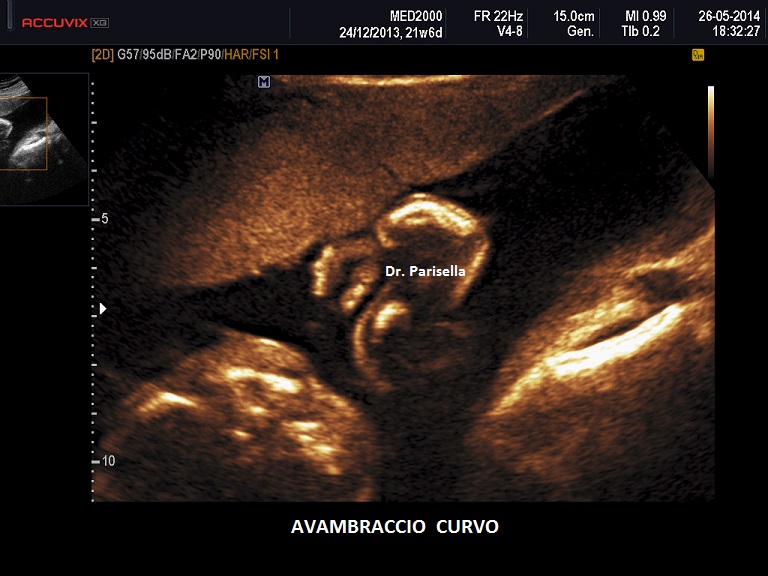

Bisogna valutare anche le alterazioni dell'asse tra segmento mesomelico e quello acromelico; tra queste rara è l'alterazione dell'asse tra avambraccio e mano (mano torta) mentre è frequente l'alterazione dell'asse tra gamba e piede ( Piede Torto ) che può essere espressione di varie patologie quali: spina bifida, idrocefalia, cromosomopatia (es. trisomia 18,.....), oligoidramnios, etc…..